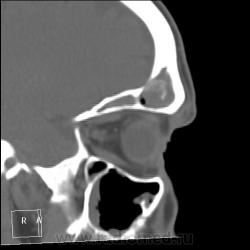

После пары менингитов на фоне синусита решили перебдеть. И вроде не зря... КТ: плотность содержимого в правой лобной пазухе 35-120 ед.Н. (мягкотканное с обызвествлением), в основной пазухе - 24 ед.Н (гнойной жидкости).

И пристеночный гайморит, и двусторонний этмоидит, и ринит, и односторонний сфеноидит, и фронтит, и очень тонкая костная пластинка между основанием передней черепной ямки и больной лобной пазухой - может быть реакция оболочек мозга...

По страшному снимку моему толком не видно, а вот на КТ множественные и разнообразные перегородки в пазухах видны хорошо. Я могу уверенно сказать только о следах жидкости в правой верхнечелюстной пазухе и субтотальном заполнении гомогенной жидкостью левой половины основной пазухи. Остальное, на мой взгляд, утолщение слизистой. Но на 100% утверждать не буду. В правой лобной я предполагаю (и только!) полипоз.

Вроде всё сказали…, но добавлю. Мне кажется, фронтит не односторонний. Эти плотные включения в правой, полипы и есть? Основных (клиновидных) пазух у каждого человека две, как и всех прочих. По обзорному снимку вижу левосторонний этмоидит. А по КТ не вижу. на каких кадрах он есть?

На 6 и 7 снимках... Справа затемнены передние ячейки решетчатых костей, слева - задние, слева процесс конечно интенсивнее.

Думаю, что полипы, "сидящие" на перегородке пазухи, сужу только по плотности - мягкотканные. А по поводу двух клиновидных пазух или разделения одной на перегородки - тут не всегда так: иногда бывает, что одна, а очень редко бывает, что и ни одной. Дайте неделю, сделаю подборку по основным пазухам на КТ.

хр.фронтит: справа с образованием обызвествленных полипообразных образований,слева- в виде утолщения слизистой оболочки. Решетчатый лабиринт клиновидной кости занят патологическим содержимым жидкостной плотности(?) с обеих сторон. Основная пазуха: справа - пристеночное утолщение слизистой, слева - тотальное заполнение. Определяется утолщение слизистой верхнечелюстных пазух, видимо воспалительного характера.